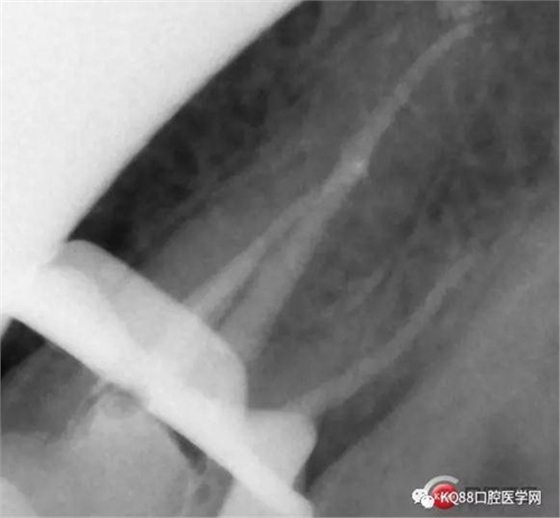

當(dāng)我第一次完成操作后,再次拍了一個插針片,發(fā)現(xiàn),距離根尖孔有1.5mm,書上說的是2mm安全區(qū),可能如果隨意點(diǎn),就直接充填了,我想說明的是,我們做根管,千萬不要馬虎,不要湊合,一定嚴(yán)謹(jǐn)?shù)膽B(tài)度,于是我重新再回到C銼,再開始耐心的預(yù)備,完成之后,再拍攝了插針片。

此次明顯可以看見根尖分開了兩個根尖孔,根管治療永遠(yuǎn)就只是那一點(diǎn),如果都只是隨便做一下,我相信,沒有復(fù)雜的牙齒,根管治療都會很簡單,態(tài)度決定一切,我不敢說我做的會很好,但是我會靜下心來,慢慢操作,這樣才能做得對的起自己和患者。于是根充完成,再次拍攝。